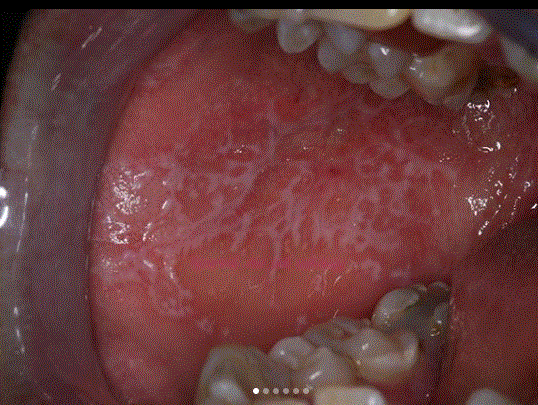

Beschreibe dieses Bild

Enoral zeigt sich ebenfalls die Auftreibung des Unterkiefers mit zentralem Ulkus und rötlichem, aufgeworfenem Randwall.